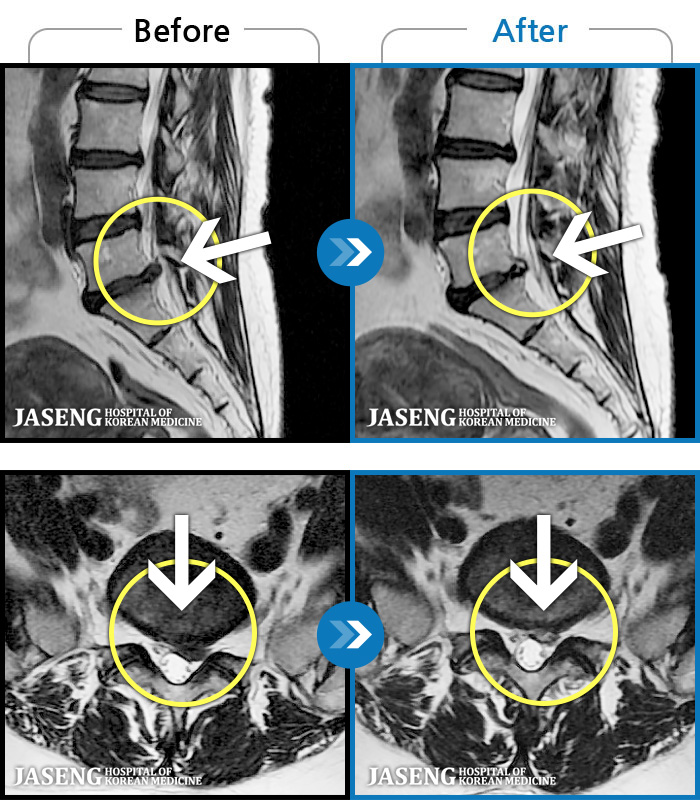

Xray 와 MRI 검사를 받았고

4번5번 척추사이 협착증과 유종이 원인이라고 하면서